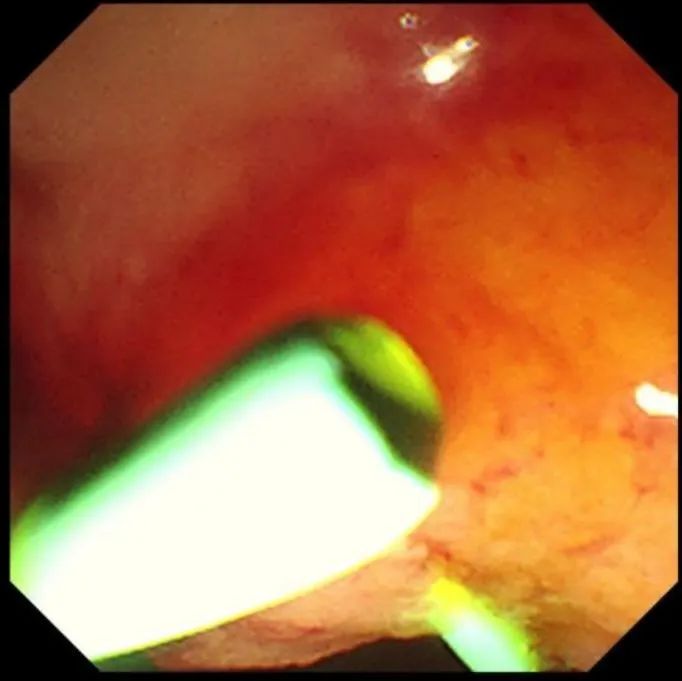

图片

支架置入成功